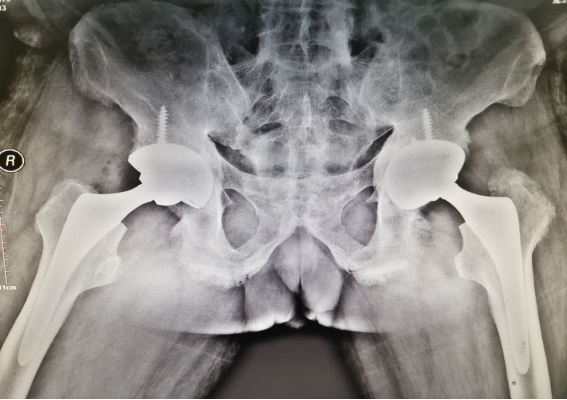

经过充分的术前准备,在麻醉科精准的麻醉下,陈天健主任凭借娴熟的操作技术和丰富的手术经验为患者成功实施了双侧髋关节置换术。术后第一天查房时,病床上的王先生随即表示疼痛已经得到了明显的缓解,更重要的是舒舒服服地睡了个好觉!

▲双侧髋关节置换非常成功